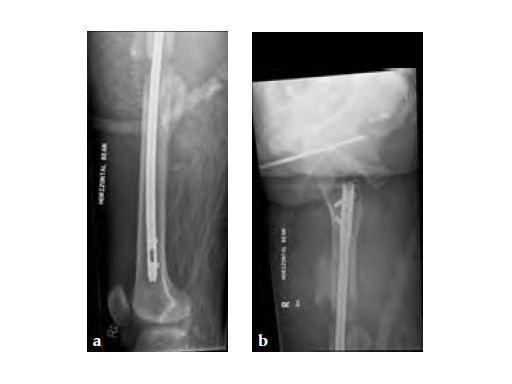

Besides severe upper limb injuries, maxillofacial injuries, a lateral compression pelvic ring injury, and pulmonary contusions, the patient sustained a 32-C3 femur fracture right.

After initial stabilization with an external fixator, the femur was nailed in a closed fashion stabilized with an AFN2 in static mode. The accurate length of the injured femur was contemplated from the uninjured leg.

9-month follow-up demonstrates that that the fracture is uniting.